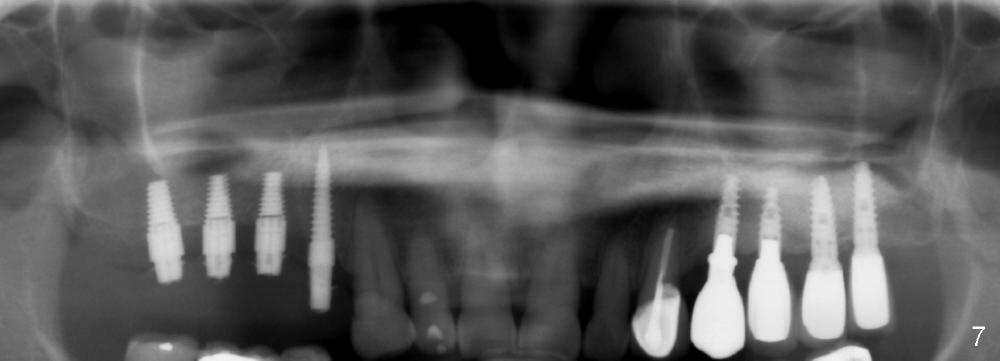

The patient has symptoms of coughing, purulent nasal discharge approximately 10 days postop in spite of the fact that oral Amoxicillin is changed to Augmentin 7 days postop. Flagyl is added 12 days postop. It appears that discharge is reduced, although coughing is persistent.

The provisional bridge is removed for exam 15 days postop. There is no oral infection. The bridge is recemented. Pan is taken (Fig.7). Finally the sinus infection resolves.

Three months postop, new bone appears to form (Fig.8 red line) on the top of the existing bone (white line). The vertical PA taken at the same time (Fig.9) shows bone formation around the other implants.

There is no apparent bone loss around the implants 13 months post immediate provisional, 5 months post cementation of non-splinted permanent restoration (Fig.10,11).